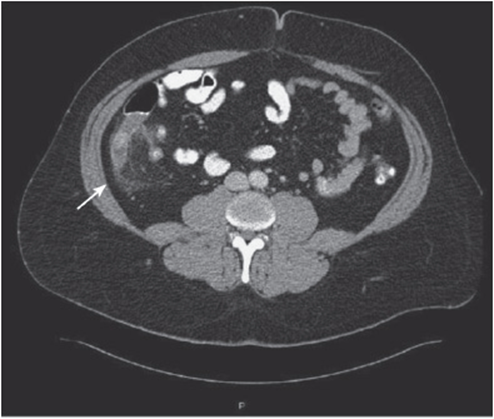

• An intra-abdominal fluid collection could be a benign/malignant tumor or an intra-abdominal abscess (see Figure 56-4).

Figure 56-4. Two intra-abdominal fluid collections, suspicious for abscesses.